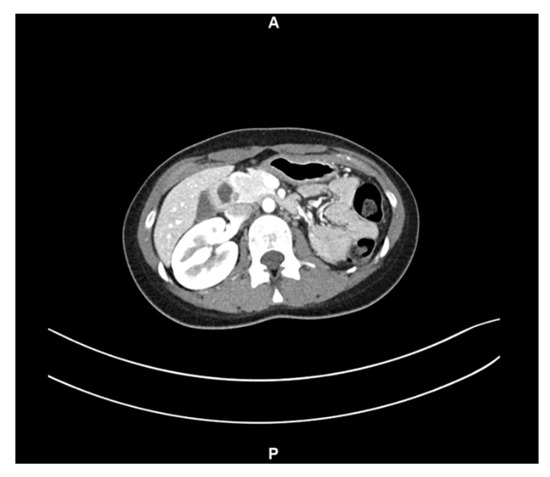

Diagnostic Challenges of OHVIRA Syndrome—A Case Report

by Paulina Tomecka, Adam Jagodziński, Justyna Łuczak, Łukasz Waszczuk and Marek Murawski

J. Clin. Med. 2026, 15(1), 190; https://doi.org/10.3390/jcm15010190 - 26 Dec 2025

Background and Clinical Significance: Herlyn–Werner–Wunderlich (HWW) syndrome, also known as OHVIRA syndrome (Obstructed HemiVagina and Ipsilateral Renal Anomaly), is a rare congenital anomaly of the female urogenital system characterized by uterine duplication, unilateral vaginal obstruction, and renal agenesis on the same side. [...] Read more.

Background and Clinical Significance: Herlyn–Werner–Wunderlich (HWW) syndrome, also known as OHVIRA syndrome (Obstructed HemiVagina and Ipsilateral Renal Anomaly), is a rare congenital anomaly of the female urogenital system characterized by uterine duplication, unilateral vaginal obstruction, and renal agenesis on the same side. The condition often remains undiagnosed until adolescence, when it presents with palpable pelvic mass, dysmenorrhea, and chronic pelvic pain. Case report: We present the case of a 13-year-old female patient diagnosed with OHVIRA syndrome following imaging studies. Surgical treatment involved incision of the vaginal septum and evacuation of accumulated blood, leading to symptom resolution and restoration of reproductive tract patency. Conclusions: This article discusses the clinical characteristics, diagnostic challenges, and the importance of early surgical intervention, emphasizing the necessity of considering this syndrome in the differential diagnosis of adolescent females with cyclic abdominal pain and renal anomalies. Early diagnosis and treatment can prevent severe health complications and improve both patients’ quality of life and fertility. Full article